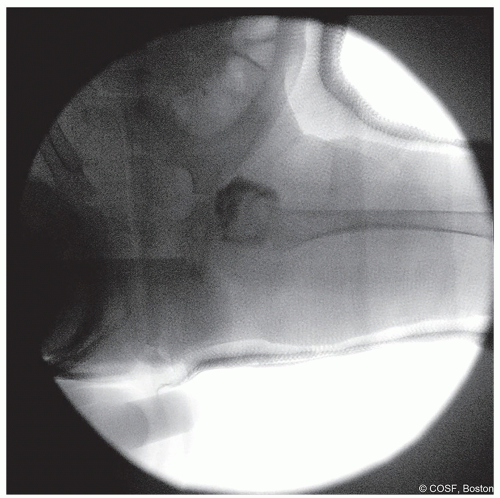

Figure 20-8 ▪ Postreduction anteroposterior (AP) view arthrogram to help confirm reduction. (Courtesy of Children’s Orthopaedic Surgery Foundation.)

In-cast fluoroscopy or plain radiographs are obtained of the operative hip(s) in both anteroposterior (AP) and iliac oblique Judet views for comparison to in-clinic imaging obtained postoperatively (Figures 20.8 and 20.9)

Figure 20-9 ▪ Postreduction iliac oblique Judet view to help confirm reduction. (Courtesy of Children’s Orthopaedic Surgery Foundation.)